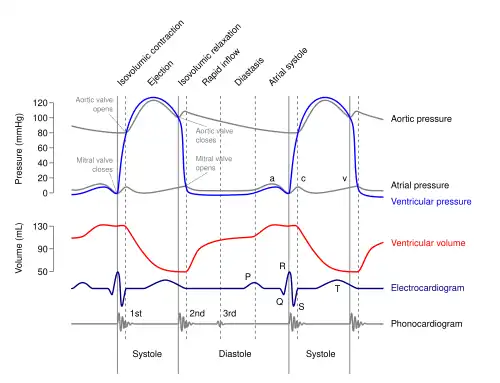

Heart sounds result from vibrations created by the closure of the heart valves. There are at least two; the first (S1) is produced when the atrioventricular valves (tricuspid and mitral) close at the beginning of systole and the second (S2) when the aortic valve and pulmonary valve (semilunar valves) close at the end of systole.[4] Phonocardiography allows the detection of subaudible sounds and murmurs and makes a permanent record of these events.[5] In contrast, the stethoscope cannot always detect all such sounds or murmurs and provides no record of their occurrence. The ability to quantitate the sounds made by the heart provides information not readily available from more sophisticated tests and provides vital information about the effects of certain drugs on the heart. It is also an effective method for tracking the progress of a patient's disease.